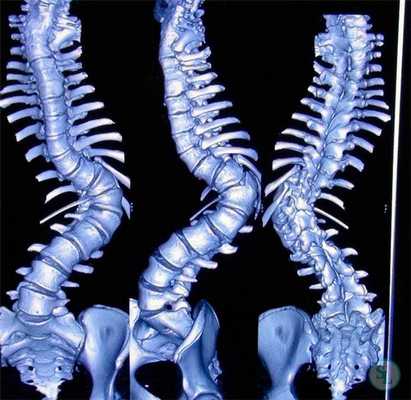

Передние доступы к грудо-поясничному отделу позвоночника впервые начали применять в 30-х годах прошлого века, однако первое поколение вентральных позвоночных фиксаторов было разработано Dwyer et al. только в 1968 г.,— этот фиксатор состоял из винтов, фиксируемых друг с другом металлическим тросом. Эти фиксаторы первого поколения позволяли корригировать деформации позвоночника во фронтальной плоскости, однако способствовали формированию значительной кифотической деформации и характеризовались тенденцией к потере стабильности из-за отсутствия необходимой ригидности конструкции.

Позднее, в 1970-х годах, Zielke et al. разработали конструкцию на основе винтов и соединяющих их ригидных стержней, которая стала следующим этапом эволюции используемых ранее фиксаторов. С тех пор прогресс уже было не остановить, и в настоящее время нам доступны самые различные системы стабилизации, которые условно можно разделить на две группы: системы, состоящие из одного ряда винтов и одного стержня, и системы, состоящие из двух рядов винтов и двух стержней.

В течение короткого времени техники вентральной коррекции при сколиотических деформациях позвоночника стали достаточно популярными и получили довольно широкое распространение. При некоторых типах искривлений вентральный спондилодез позволяет ограничиться меньшим числом стабилизируемых уровней, чем задний. Аналогичный рентгенологический результат при вентральном спондилодезе достигается при стабилизации в среднем на 2,5 уровня меньше, чем при заднем.

Вентральная коррекция позволяет приложить более значительные аксиальные усилия, необходимые для коррекции ротационного смещения позвонков, а также в сравнении с гибридными конструкциями позволяет корригировать гипокифоз, нередко наблюдающийся у пациентов с подростковым идиопатическим сколиозом. Передние вмешательства также позволяют добиться более эффективной коррекции компенсаторных, не подвергающихся спондилодезированию дуг искривления, вероятность развития их декомпенсации со временем также ниже. Следует, однако, отметить, что с появлением транспедикулярных фиксаторов и методик прямой деротации тел позвонков из заднего доступа передние доступы, за исключением отдельных клинических ситуаций, утратили былую популярность.